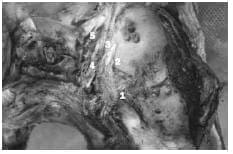

2. Troncos vasculares dependientes de la A. Carótida Interna derecha intra cavernosos.

1-Tronco Meningo-Hipofisiario

2-Ramo Meníngeo Dorsal.

3-Tronco Infero lateral

4-VI par

5-Segmento Supraclinoideo

6- Segmento Subclinoideo. III, IV, V1 replegados.